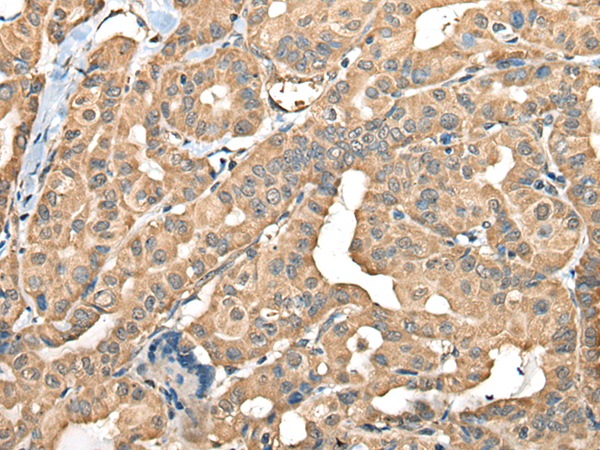

IHC positive control: |

Human thyroid cancer |